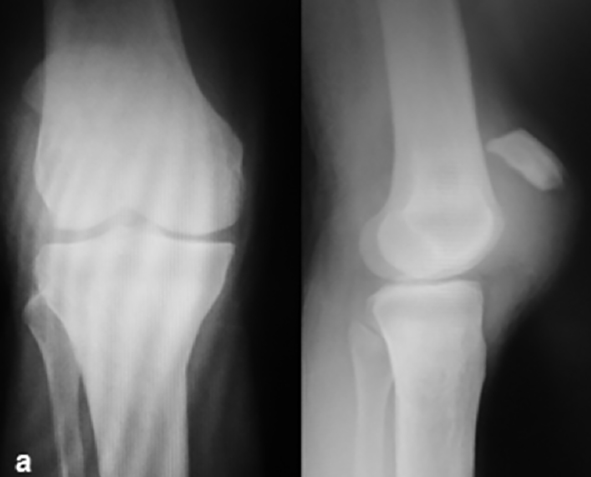

El primer caso clínico corresponde a una mujer, de 31 años de edad, con antecedente de IRC estadio V, hipertensión arterial, con traumatismo en hiperflexión de ambas rodillas que produjo una avulsión de la inserción distal del tendón patelar derecho y tendón cuadricipital izquierdo, la cual fue tratada quirúrgicamente con reparación aguda de tendón cuadricipital izquierdo por medio de túneles transóseos a la patela y reconstrucción del tendón patelar derecho con autoinjerto de tendón cuadricipital (TC) ipsilateral, como recurso inmediato en vista del mal estado, cambios degenerativos y pérdida de tejido viable observado durante la cirugía. Se protegió la reparación con cerclaje de alambre que fue retirado a los 8 meses (Figura 1).